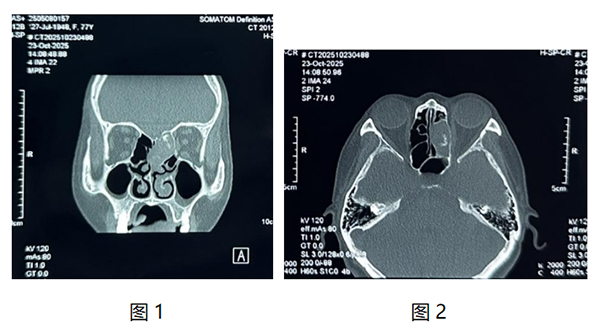

我(wo)院耳鼻咽喉頭頸外科(ke)近日(ri)爲(wei)一(yi)名(míng)77歲老年(nian)患者實施鼻內(nei)鏡下篩窦開放+窦內(nei)病變清(qing)除術(shù),患者因“左側頭痛多(duo)涕1月”到(dao)我(wo)院檢(jian)查,入院查體(ti)可(kě)見左側鼻腔中(zhong)鼻甲水腫,上鼻道大(da)量棕黃色幹痂。鼻窦CT檢(jian)查可(kě)見左側篩窦內(nei)軟組織影,內(nei)部(bu)密度不均。(如圖1、2)